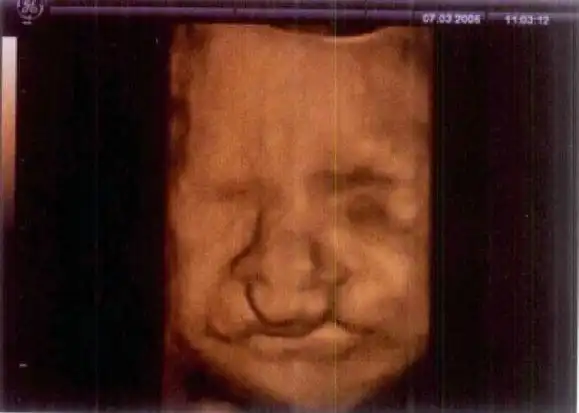

生了唇腭裂宝宝怎么办 —— 什么是唇裂?